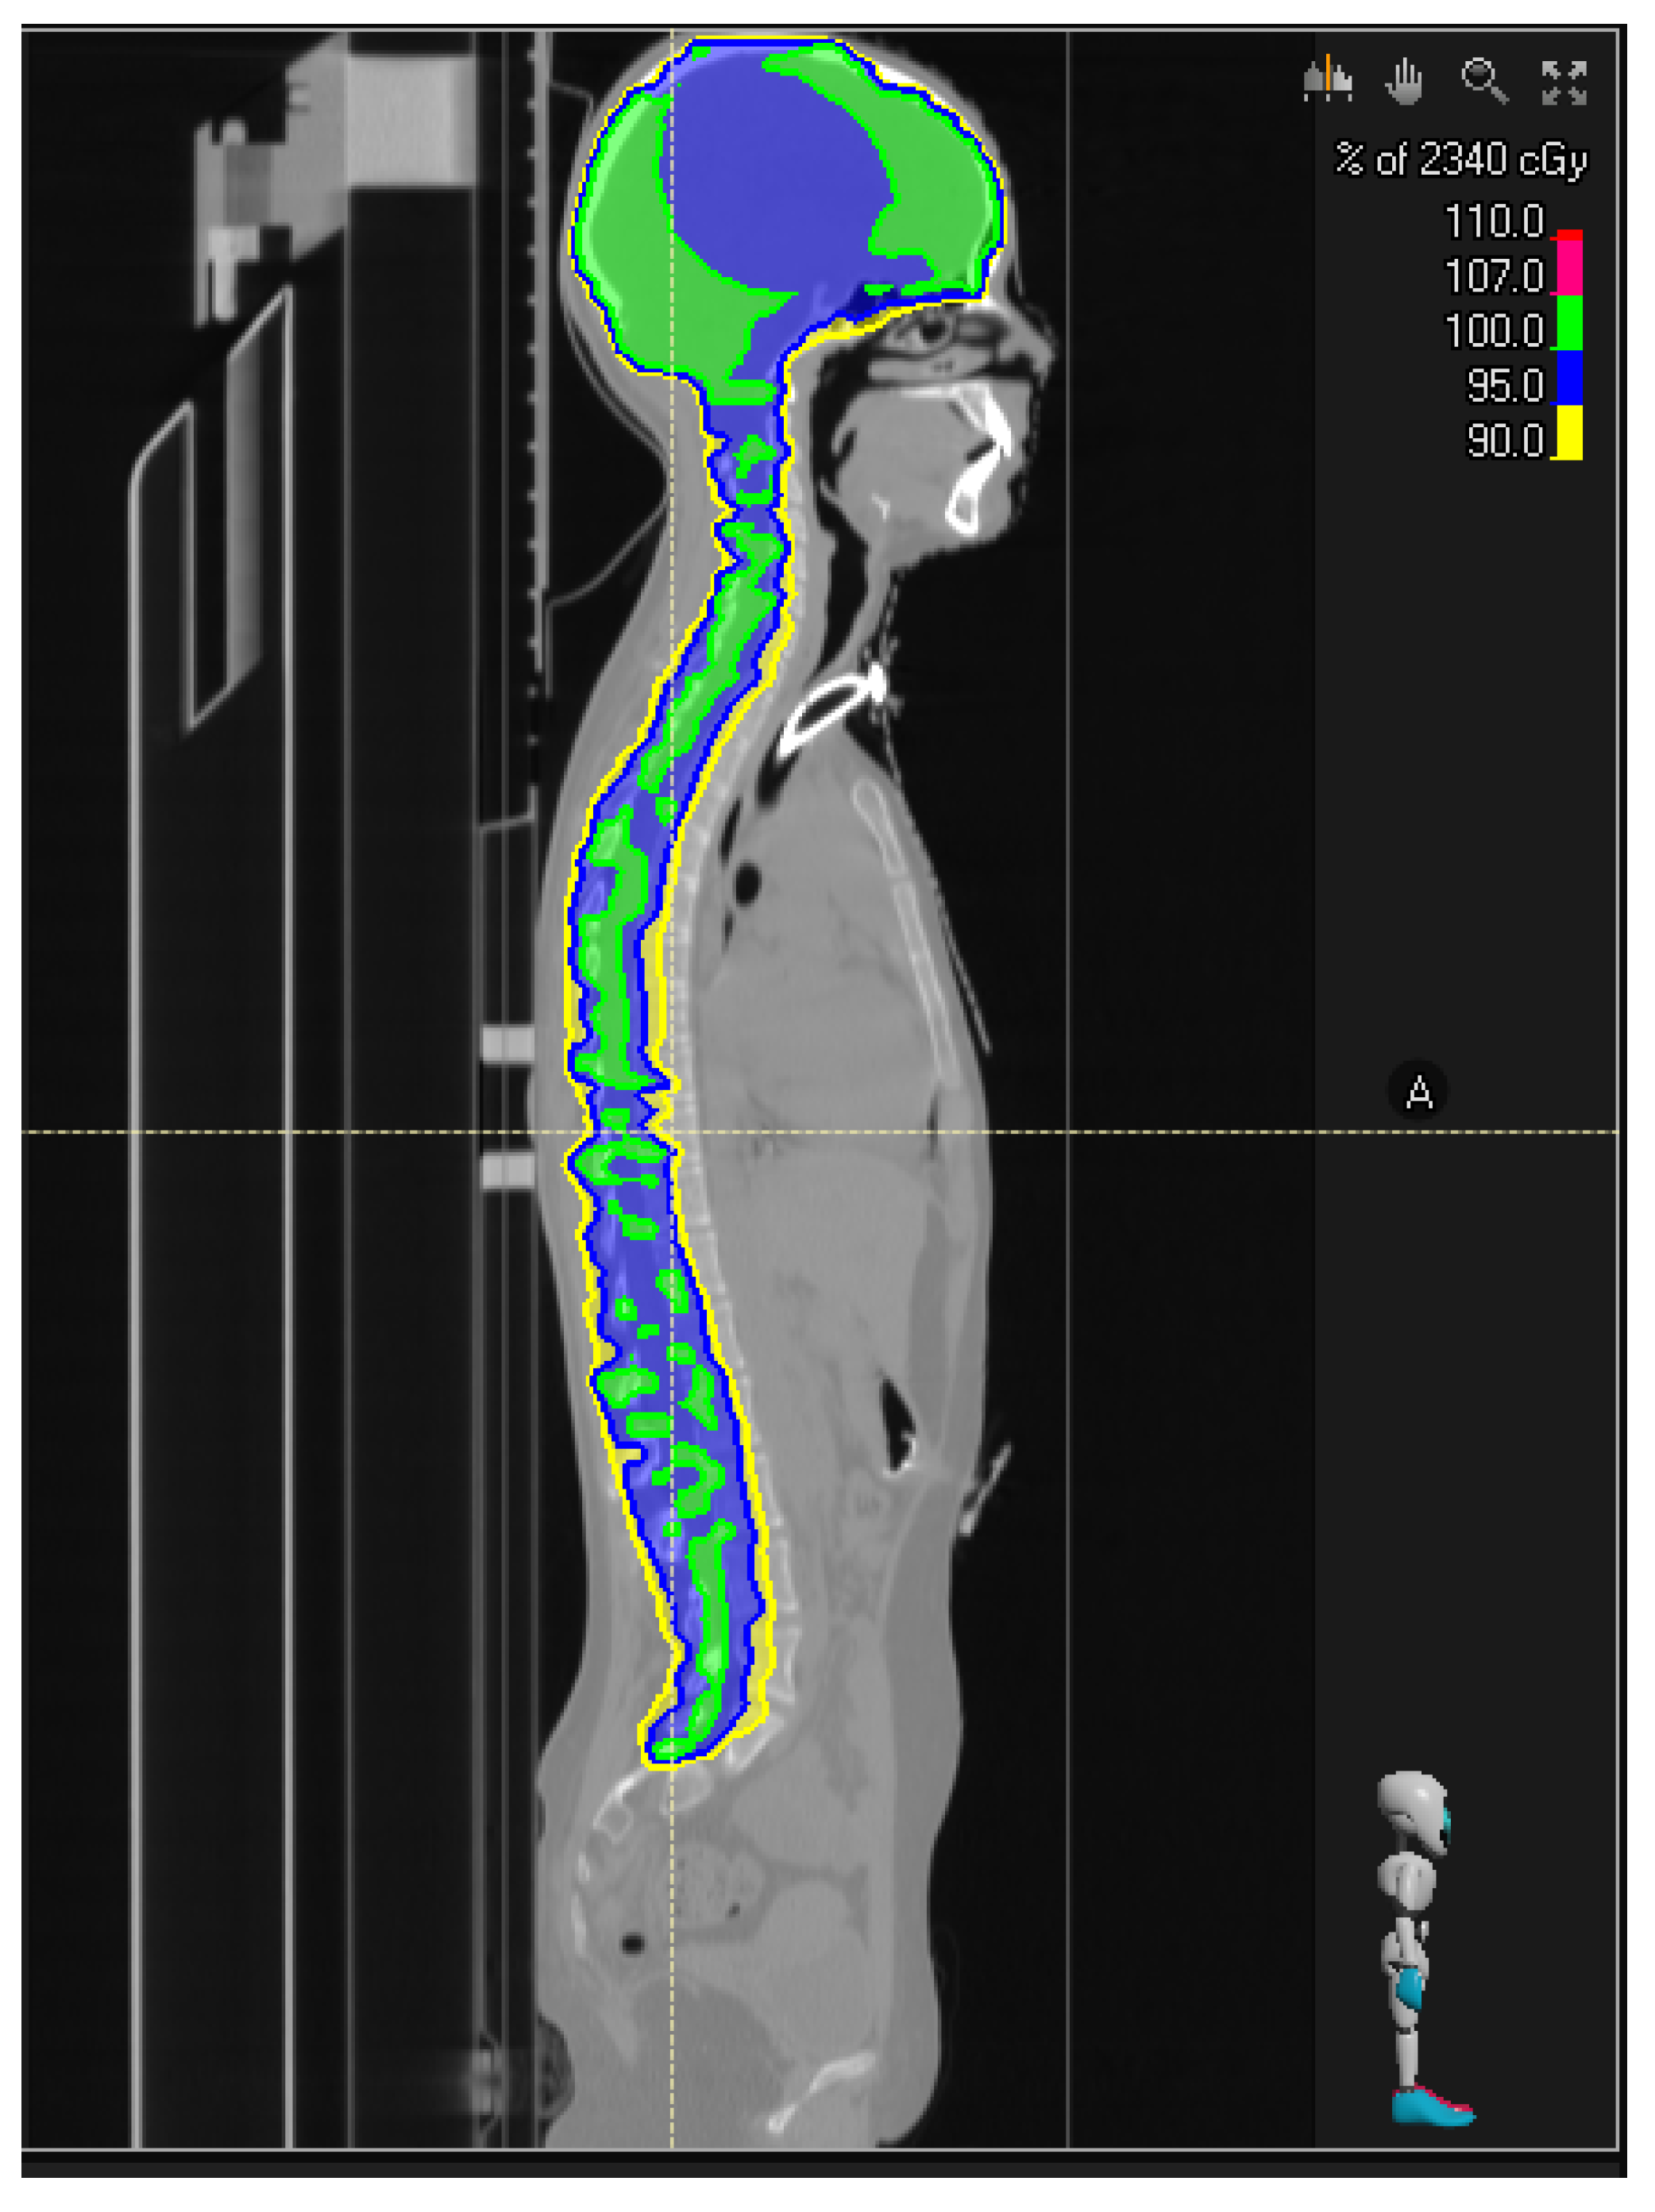

Beyond the time to first recurrence, specific patterns of tumor recurrence, such as leptomeningeal dissemination, can influence treatment strategies. For example, tailoring radiotherapy based on tumor aggressiveness in terms of dose and volume is possible. Given the higher malignancy associated with the H3K27M mutation profile, a slightly increased dose could hypothetically be used for the second course of local irradiation, while irradiation of the entire craniospinal axis could help control both local and leptomeningeal compartments (Figure 1).

Figure 1.

Craniospinal irradiation for improving control of leptomeningeal department.